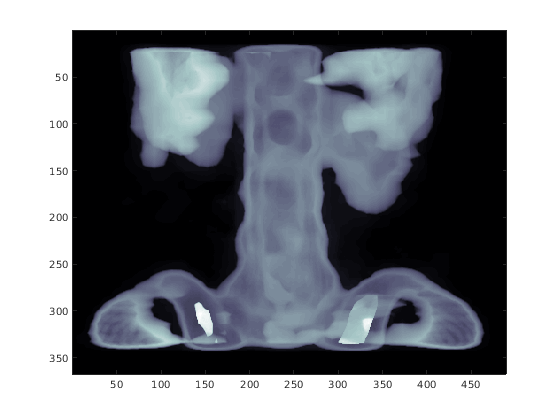

Загрузите spine набор данных, который возвращает изображение X и связанные с ним map палитры. Отобразите X использование image и установите палитру равной map.

load spine

image(X)

colormap(map)